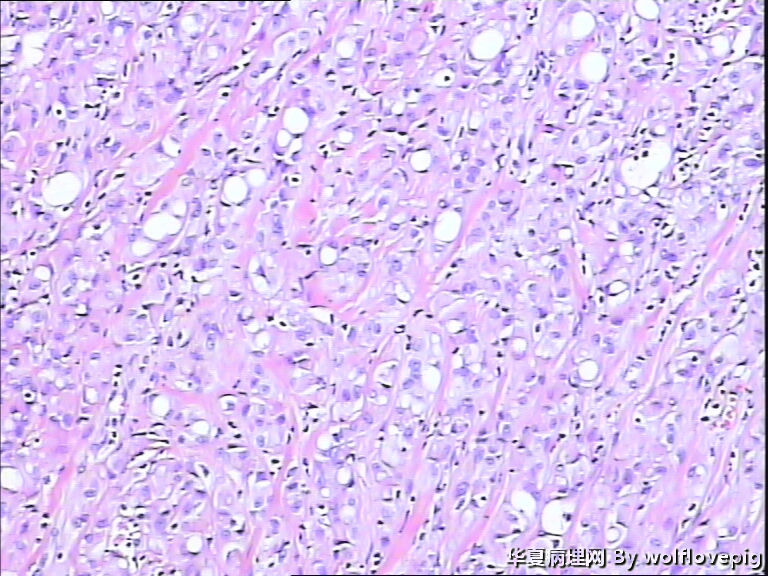

男,60y,左阴囊包块6月,位于附睾尾与睾丸之间,无粘连。灰白结节一个0.7*0.3*0.3,切面灰白、实体 、质韧。

典型的腺瘤样瘤

同意腺瘤样瘤